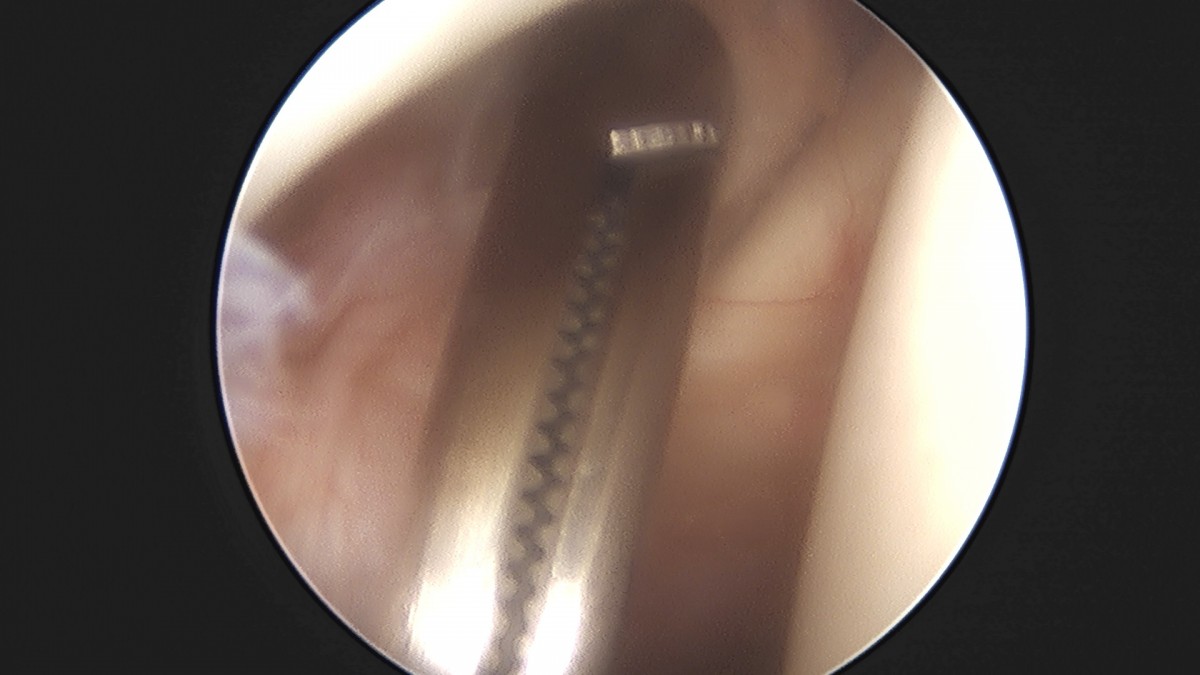

이재상원장님 어깨 석회 제거술 조광O 환자

dae765e4d9ac96aee867c9d6292d8784_1758004691_9404.jpg